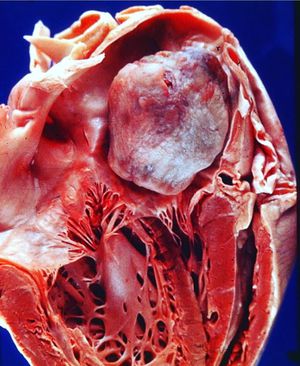

A tumor in the heart - atrial myxoma" The left atrium has been opened to reveal the most common primary cardiac neoplasm - an atrial myxoma. These benign masses that arises from remnants of subendocardial vasoformative reserve cells, which are primitive mesenchymal cells that are normally involved in the supportive structure of the endocardium. They most often located in the fossa avails and endocardium of the atrial septum, but can arise on a valve or in a ventricle. They can produce a "ball valve" effect by intermittently occluding the atrioventricular valve orifice. Embolization of fragments of tumor may also occur. Myxomas are easily diagnosed by echocardiography. They may also be seen with chest CT scan and with magnetic resonance angiography. On gross pathology, a gelatinous, irregular surface that fills the left atrium is characteristic finding of myxoma. Common physical examination findings of cardiac myxoma include murmur and abnormal heart sounds that change when the patient changes positions. Complications that can develop are commonly arrhythmias, pulmonaryedema, peripheral emboli, metastasis, blockage of the mitral heart valve. Surgery is the mainstay of treatment for myxomas. 📷 •Medicogram• #letslearn #cardiomyopathy #cardiology #myxoma #heart #disease #cancer #trending #now #tbt #medicine #doctors #health #medicogram